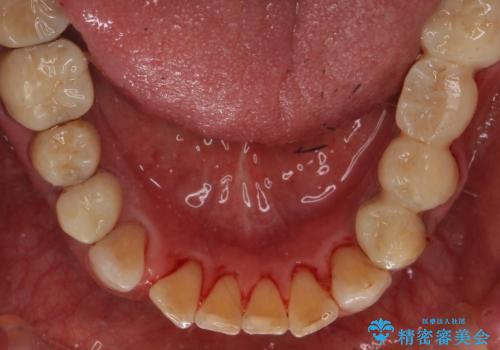

ステインがたくさん付着していたので、エアフローを用いてステインを除去しました。そのため、直後の写真は歯肉からの出血が見られます。

まず歯石取りを行い歯肉の状態を改善後、後日PMTC30分コースをしました。